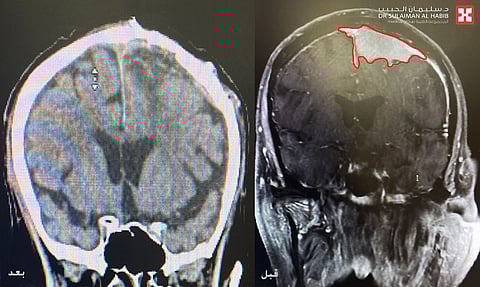

موضحاً أن الفريق الطبي أخضعه لحزمة من الفحوصات الطبية الدقيقة والتي شملت، الرنين المغناطيسي (M.R.I) والتصوير الطبقي لشرايين الدماغ (CT angiography)، وقد كشفت النتائج عن وجود ورم كبير بحجم (6×5×6) سم متمركز في منتصف الدماغ بالقرب من مراكز منطقة الحركة للأطراف العلوية والسفلية ومتداخل مع الشريان الأعظم، كما نتج عن هذا الورم حدوث إزاحة وضغط شديد على الدماغ ووجود انسداد في عدد من الشرايين المحيطة به.

وعقب الدراسة لكامل معطيات النتائج ، اتخذ قرار سرعة التدخل الجراحي لاستئصال الورم، مفيداً بأن العملية استغرقت 6 ساعات تحت التخدير العام، وتم فيها استخدام أجهزة الميكروسكوب الجراحي المتطور وعمل معايرة للدماغ، ومن ثم تحرير الورم من تشعباته وتخفيف الضغط على الدماغ مع تنظيف أجزاء الورم المتداخلة في الشريان الأعظم ومن ثم استئصاله بالكامل، مع المحافظة على سلامة جميع الشرايين والأعصاب المحيطة بالورم، نقل بعدها إلى العناية المركزة مع وضعه تحت العناية الحثيثة والمراقبة على مدار الساعة.

وقال الدكتور هاني عبد العزيز في اليوم الثالث تحسنت حالة المراجع ،حيث تم نقله لجناح التنويم، مع إخضاعه لفحوصات بالتصوير المقطعي، والتي أثبتت استئصال الورم بشكل كامل ونجاح العملية وانتهاء نوبات التشنج والحركات اللارادية، وخرج من المستشفى في اليوم الرابع وهو بصحة جيدة.